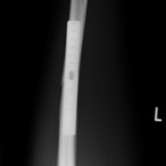

Röntgenbilder